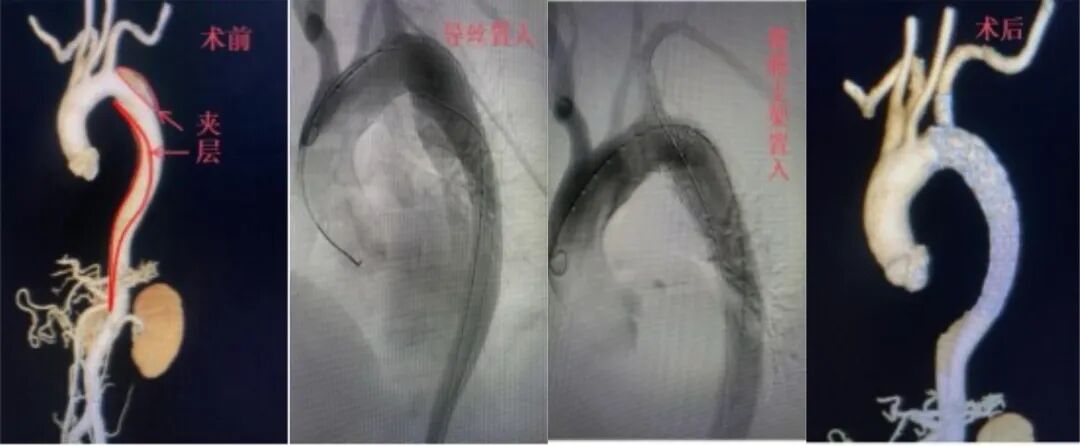

去年12月,一名51岁男性因突发重度高血压急诊入院,血压高达200/100mmHg,确诊腹主动脉夹层,随时可能破裂。急诊紧急降压稳命后,肖志异团队实施胸主动脉支架+分支支架置入术。术后患者血压控制良好,顺利康复出院。